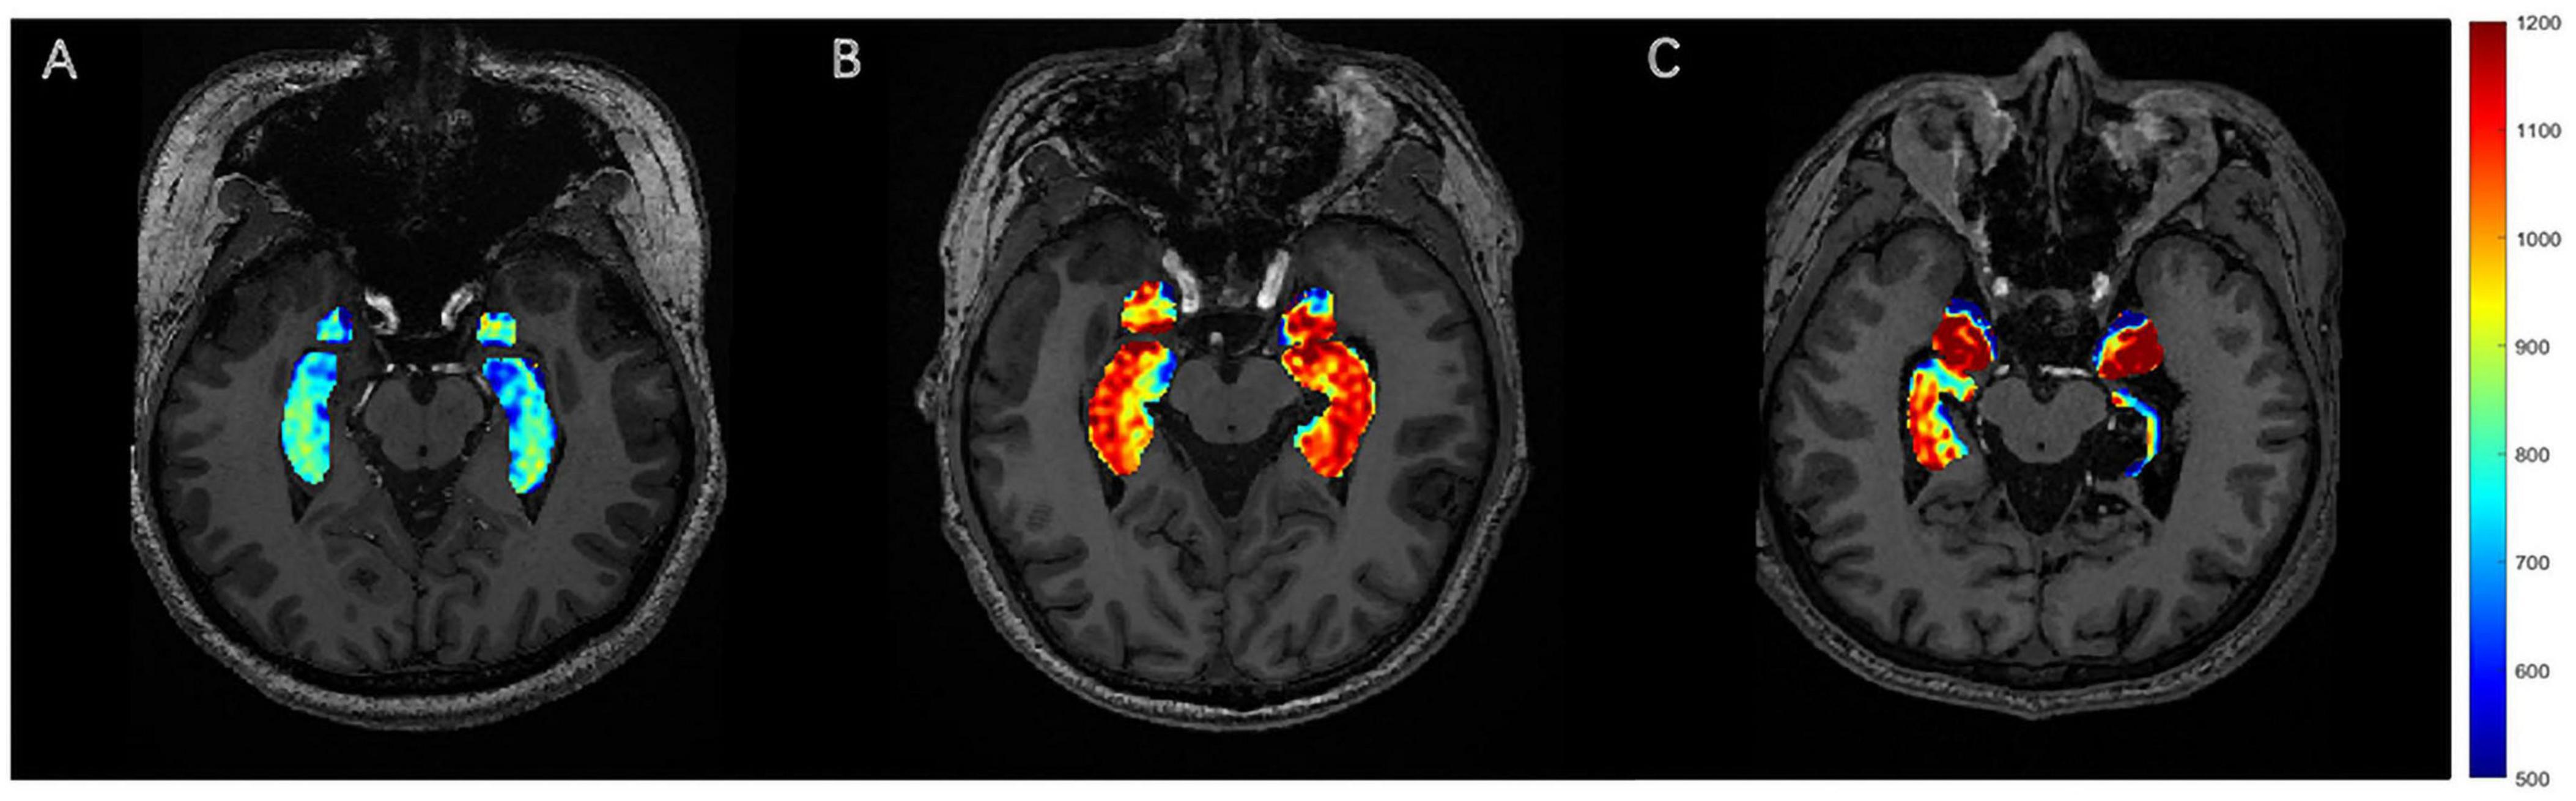

ABSTRACT Objectives: This study aimed to investigate the diagnostic value of combined glutamate chemical exchange saturation transfer (GluCEST) imaging and γ-aminobutyric acid (GABA)-edited proton magnetic resonance spectroscopy (1H-MRS) in localizing epileptogenic foci and differentiating drug-resistant epilepsy (DR) from drug-responsive epilepsy (DRES) in temporal lobe epilepsy (TLE) using 5T MRI. Methods: Twenty-four TLE patients (13 left, 11 right) and 25 age-/gender-matched healthy controls (HCs) underwent GluCEST and MEGA-PRESS MRS at 5T MRI. Directional asymmetry indices (DAIglu_H for hippocampus, DAIglu_A for amygdala) and a novel composite biomarker (DAIglu_GABA) integrating GluCEST asymmetry and GABA/Cr ratios were analyzed. Another asymmetry metric was employed to discriminate the left and right TLE groups (DAIglu_H(epi) for hippocampus, DAIglu_A(epi) for amygdala). Subgroup comparisons (HC vs. DR vs. DRES) and receiver-operating characteristic (ROC) analyses were performed. Results: GluCEST-derived hippocampal asymmetry (DAIglu_H(epi)) effectively lateralized epileptogenic foci (AUC = 0.86). The DRES patients exhibited elevated DAIglu_H (adjusted p < 0.001) and reduced GABA/Cr (adjusted p = 0.015) compared to HCs. The DAIglu_GABA index increased in the DRES subgroup compared to HCs (adjusted p < 0.001). Moreover, DAIglu_GABA levels were found to be significantly lower in the DR subgroup in comparison to the DRES subgroup (adjusted p = 0.009). Conclusions: Multimodal 5T MRI integrating GluCEST and GABA-MRS provides a clinically feasible tool for lateralizing epileptogenic foci and stratifying drug resistance in TLE. The observed excitatory-inhibitory imbalance dynamics suggest distinct neurometabolic profiles underlying DR and DRES, advancing personalized therapeutic strategies.